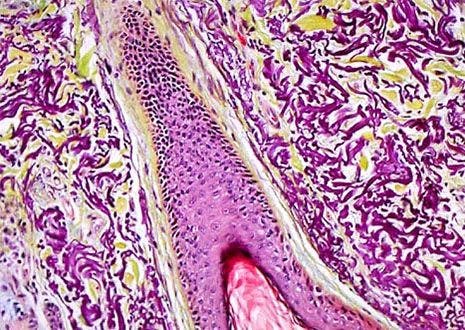

Skin Hair Follicle

Hair does not exist and grow alone, but is part of thepilosebaceous system, which also includes follicles, papillae, and sebaceous glands. A typical human has approximately 100,000 hairs on his or her scalp and loses about 50 to 100 strands a day.